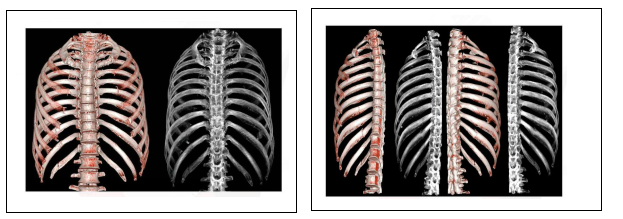

三.骨科系统:

可以沿任意轴观察骨骼,任意角度重建可以发现隐匿的骨折、复杂多发骨折、骨折手术效果评估。

肋骨成像(T8-T10右后肋骨折)